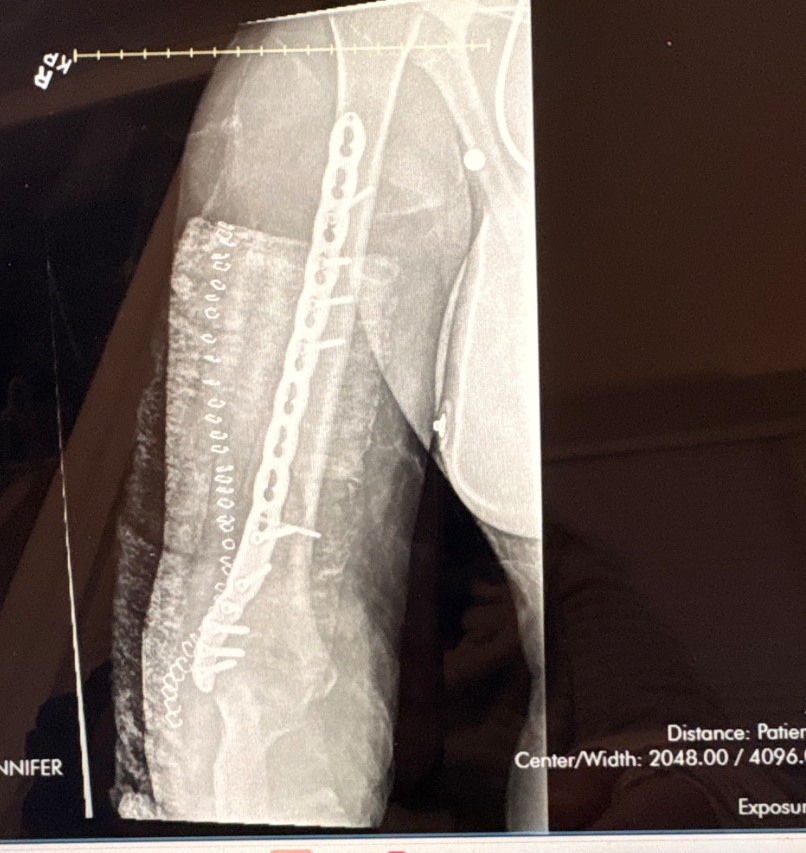

My daughter Zayden (Kylee) was involved in a major car accident on 3/20. The ambulance did not arrive on the scene until over an hour after the accident and did not provide proper care to her. She was taken to the trauma unit at Beth Israel Hospital in Beverly, where she had several tests and scans completed and ultimately went into emergency surgery to repair her humerus that snapped completely. They put in a large steel plate from her shoulder down past her elbow and 11 screws. When the bone snapped, it went into her radial nerve, which has now caused her to lose all motion and feeling in her wrist and her fingers except for being able to bend a couple of fingers down slightly. The hope is that with time she will get feeling and movement back, but it is not guaranteed. And if she does, it can take up to 6 months.